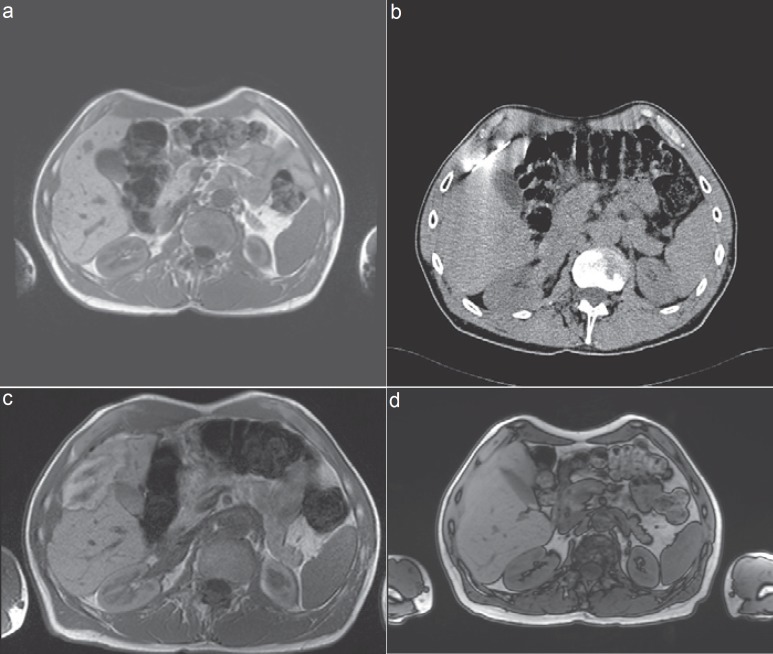

Methods: Liver-directed therapies are classified into vascular transarterial techniques such as chemoperfusion (TACP), chemoembolization (TACE), radioembolization (selective internal radiation therapy (SIRT)), and chemosaturation, as well as thermal ablation techniques like microwave ablation (MWA), radiofrequency ablation (RFA), laser-induced thermotherapy (LITT), cryotherapy, and irreversible electroporation (IRE). The authors searched the database PubMed using the following terms: 'image-guided tumor ablation', 'thermal ablation therapies', 'liver metastases of uveal melanoma', 'neuroendocrine carcinoma', 'breast cancer', and 'non-colorectal liver metastases'.

Results: Various combinations of the above-mentioned therapy protocols are possible. In neuroendocrine carcinomas, oligonodular liver metastases are treated successfully via thermal ablation like RFA, LITT, or MWA, and diffuse involvement via TACE or SIRT. Although liver involvement in breast cancer is a systemic disease, non-responding nodular metastases can be controlled via RFA or LITT. In ocular or cutaneous melanoma, thermal ablation is rarely considered as an interventional treatment option, as opposed to TACE, SIRT, or chemosaturation. Rarely liver-directed therapies are used in pancreatic cancer, most likely due to problems such as biliary digestive communications after surgery and the risk of infections. Rare indications for thermal ablation are liver metastases of other primary cancers like non-small cell lung, gastric, and ovarian cancer.